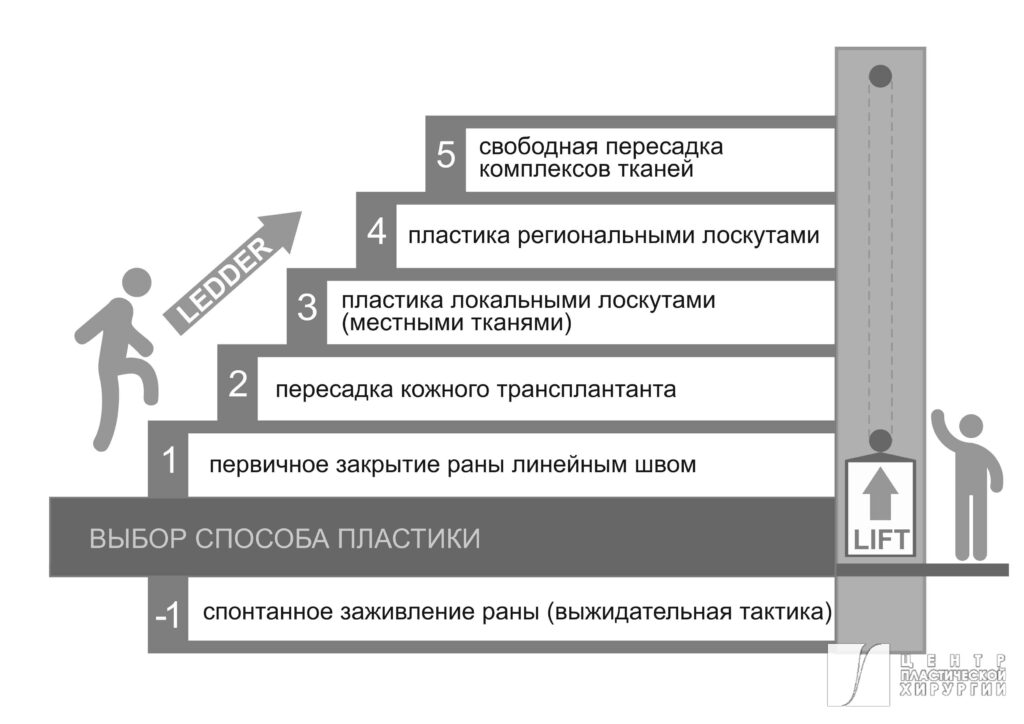

Для успешной пластической реконструкции при раневых дефектах в области нижних конечностей необходим комплексный подход [2], который включает в себя рассмотрение возможности применения соответствующих хирургических методов и критических факторов пациента, которые могут ограничивать применение сложных или длительных операций. Традиционная система приоритетов в отношении методов реконструктивной хирургии подразумевает использование концепции, известной под названием «реконструктивной лестницы» (“reconstructive ladder”) [9,10,11]. Последняя приемлема и для реконструкции нижних конечностей, как первый принцип. Однако, разрабатывая план лечения хирург не должен использовать ее как догму. Предпочтительнее будет выбор методики с учетом функциональности реконструированных тканей в будущем. Для примера: на опорной поверхности стопы, даже когда раневой дефект мог бы быть закрыт более простым методом – кожным аутологичным трансплантатом, предпочтительнее использовать транспозиционный или даже свободный лоскут с хорошо развитой дермой и гиподермой. Несмотря на то, что такой план будет изначально сложнее и риски выше, оправданием может служить цель такой реконструкции, когда планируется замещение дефекта новым покровом, наиболее соответствующим утраченному. В случае успешной реализации это обеспечит значительное улучшение конечного результата и/или сокращение количества этапных вмешательств. Таким образом, вторым принципом можно назвать «реконструктивный лифт» («reconstructive elevator»), который утверждает, что самый простой метод не всегда будет наилучшим выбором [12], а опыт хирурга позволит выбрать наилучший уровень инициально (Рис. 1). Кроме того, еще одним, третьим, принципом является наличие необходимых навыков и предпочтений у хирургической бригады, а также ресурсов для технической реализации хирургического плана и послеоперационной реабилитации [13]. Иными словами, этот принцип утверждает, что наилучшим выбором будет тот метод, которым уверенно владеет ведущий хирург и для реализации плана оперативного лечения есть необходимые возможности.

Рис. 1. Система приоритетов в отношении выбора методов пластики подразумевает поступательный переход от простых методов к сложным методам по принципу «реконструктивной лестницы» или по принципу «реконструктивного лифта».